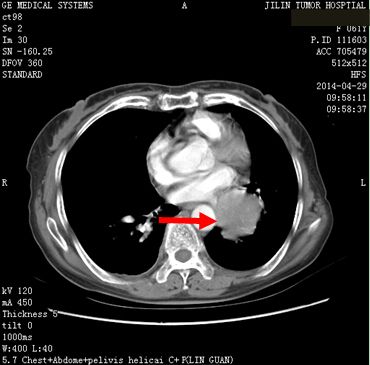

患者任某,女,60岁,患者因刺激性咳嗽3个月,右上腹部疼痛2个月于2014年4月11日就诊。入院后行肺增强CT、全腹增强CT;:左肺下叶支气管开口周围见类圆形肿块影,大小约为4.75×4.54cm,肿块包绕左肺下静脉及左肺下动脉干,肿块不均匀强化,左肺下叶支气管开口截断,左肺下叶内前基底段肺组织实变。左肺门见肿大淋巴结与肺门肿块融合。肝脏大小及形态未见确切异常,肝实质内弥漫性分布低密度肿块影,肿块融合成团,约占据整个肝脏,增强检查环形强化,选择病灶2.81×2.68cm,腹腔内见多个肿大淋巴结,融合成团,包绕邻近组织,较大约为3.21×2.57cm,左侧肾上腺见类圆形肿块影,大小约为2.49×1.99cm,增强检查略强化。明确诊断为:左肺下叶小细胞肺癌(T2aN1M1b)Ⅳ期,广泛期、左肺门淋巴结转移、 多发肝转移、腹腔淋巴结转移。符合我院正在进行的Ipilimumab联合EP治疗广泛期小细胞肺癌的III期临床研究,给予入组。于2014年5月1日开始给予EP方案化疗(VP-16,100mg/m2,157mg,d1-3;DDP,75mg/m2,118mg,d1),共给予化疗4周期,第3周期开始给予加用Ipilimumab单抗(10mg/kg),现患者已应用2周期,无明显严重不良反应发生。2周期后疗效判定:靶病灶1、左肺内病灶消失,2、左肾上腺转移病灶11.6×9.5=110.2,3、肝转移病灶11.3×9.1=102.83。靶病灶乘积之和213.03,疗效判定PR,非靶病灶:1、肝内其他转移病灶,存在,2、腹腔其他转移淋巴结,存在,疗效判定SD,总体疗效判定PR。现患者仍在继续用药中。

2014年4月29日治疗前